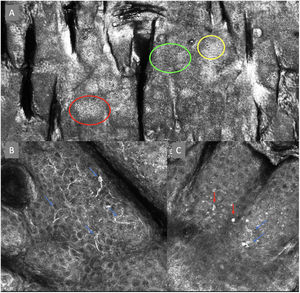

ResultsFourteen out of the 14 experts invited to participate via e-mail responded to Delphi's 1st round which included a total of 52 English terms and their proposed Spanish translations. Twenty-eight of these terms were for melanocytic lesions, and 24 for non-melanocytic lesions. The 24 terms for non-melanocytic lesions correspond to 9 terms for basal cell carcinoma, 9 for squamous cell carcinoma and actinic keratosis, and 6 for solar lentigo, seborrheic keratosis, and lichenoid keratosis. In Delphi's 1st round, > 80% agreement was reached for the “strongly agree” alternative in 25 out of 28 terms for melanocytic lesions (Table 1), including honeycomb pattern, cobblestone pattern, disorganized epidermis (Fig. 1A); pagetoid cells, dendritic cells, pleomorphic cells, round cells (Fig. 1B and C), poorly demarcated papillae (Fig. 2A), junctional thickening (Fig. 2B), and atypical cells (Fig. 2C and D); 19 out of 24 terms for non-melanocytic lesions; 7 out of 9 terms for basal cell carcinomas (Table 2) including polarization, clefting, and peripheral palisading (Fig. 3B); 8 out of 9 terms for squamous cell carcinoma and actinic keratosis (Table 3), including architectural disorder, and atypical honeycomb pattern (Fig. 3A); and in 4 out of 6 terms for solar lentigo, seborrheic keratosis, and lichenoid keratosis, including milium cysts, keratin-filled epidermal invaginations, and bulbous projections (Table 4).

Confocal microscopy images in high epidermal layers. Top (A). Presence of honeycomb pattern (red circle), cobblestone pattern (yellow circle), and disorganized epidermis with dendritic cells (green circle). Bottom. Detail of pagetoid growth cells. Left (B). Dendritic cells (blue arrow). Right (C). Pleomorphic, round (red arrow), and dendritic cells (blue arrow).